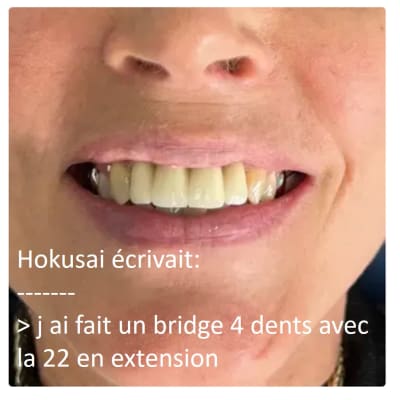

Hokusai écrivait:

-------

> une autre anomalie dans ce cas, donc vous avez fait le choix de poser les

> implants distaux en supra-osseux pour simplifier le cas afin d utiliser des

> piliers droits... mais a cote de ca fallait metttre en charge le jour de la pose

> ? quelle est l utilite ?